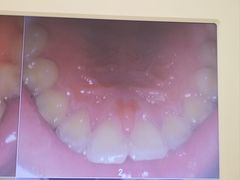

• 圣贝口腔(海淀店)

• -圣贝口腔(海淀店)

牛油果酱空心菜 | 24-07-17